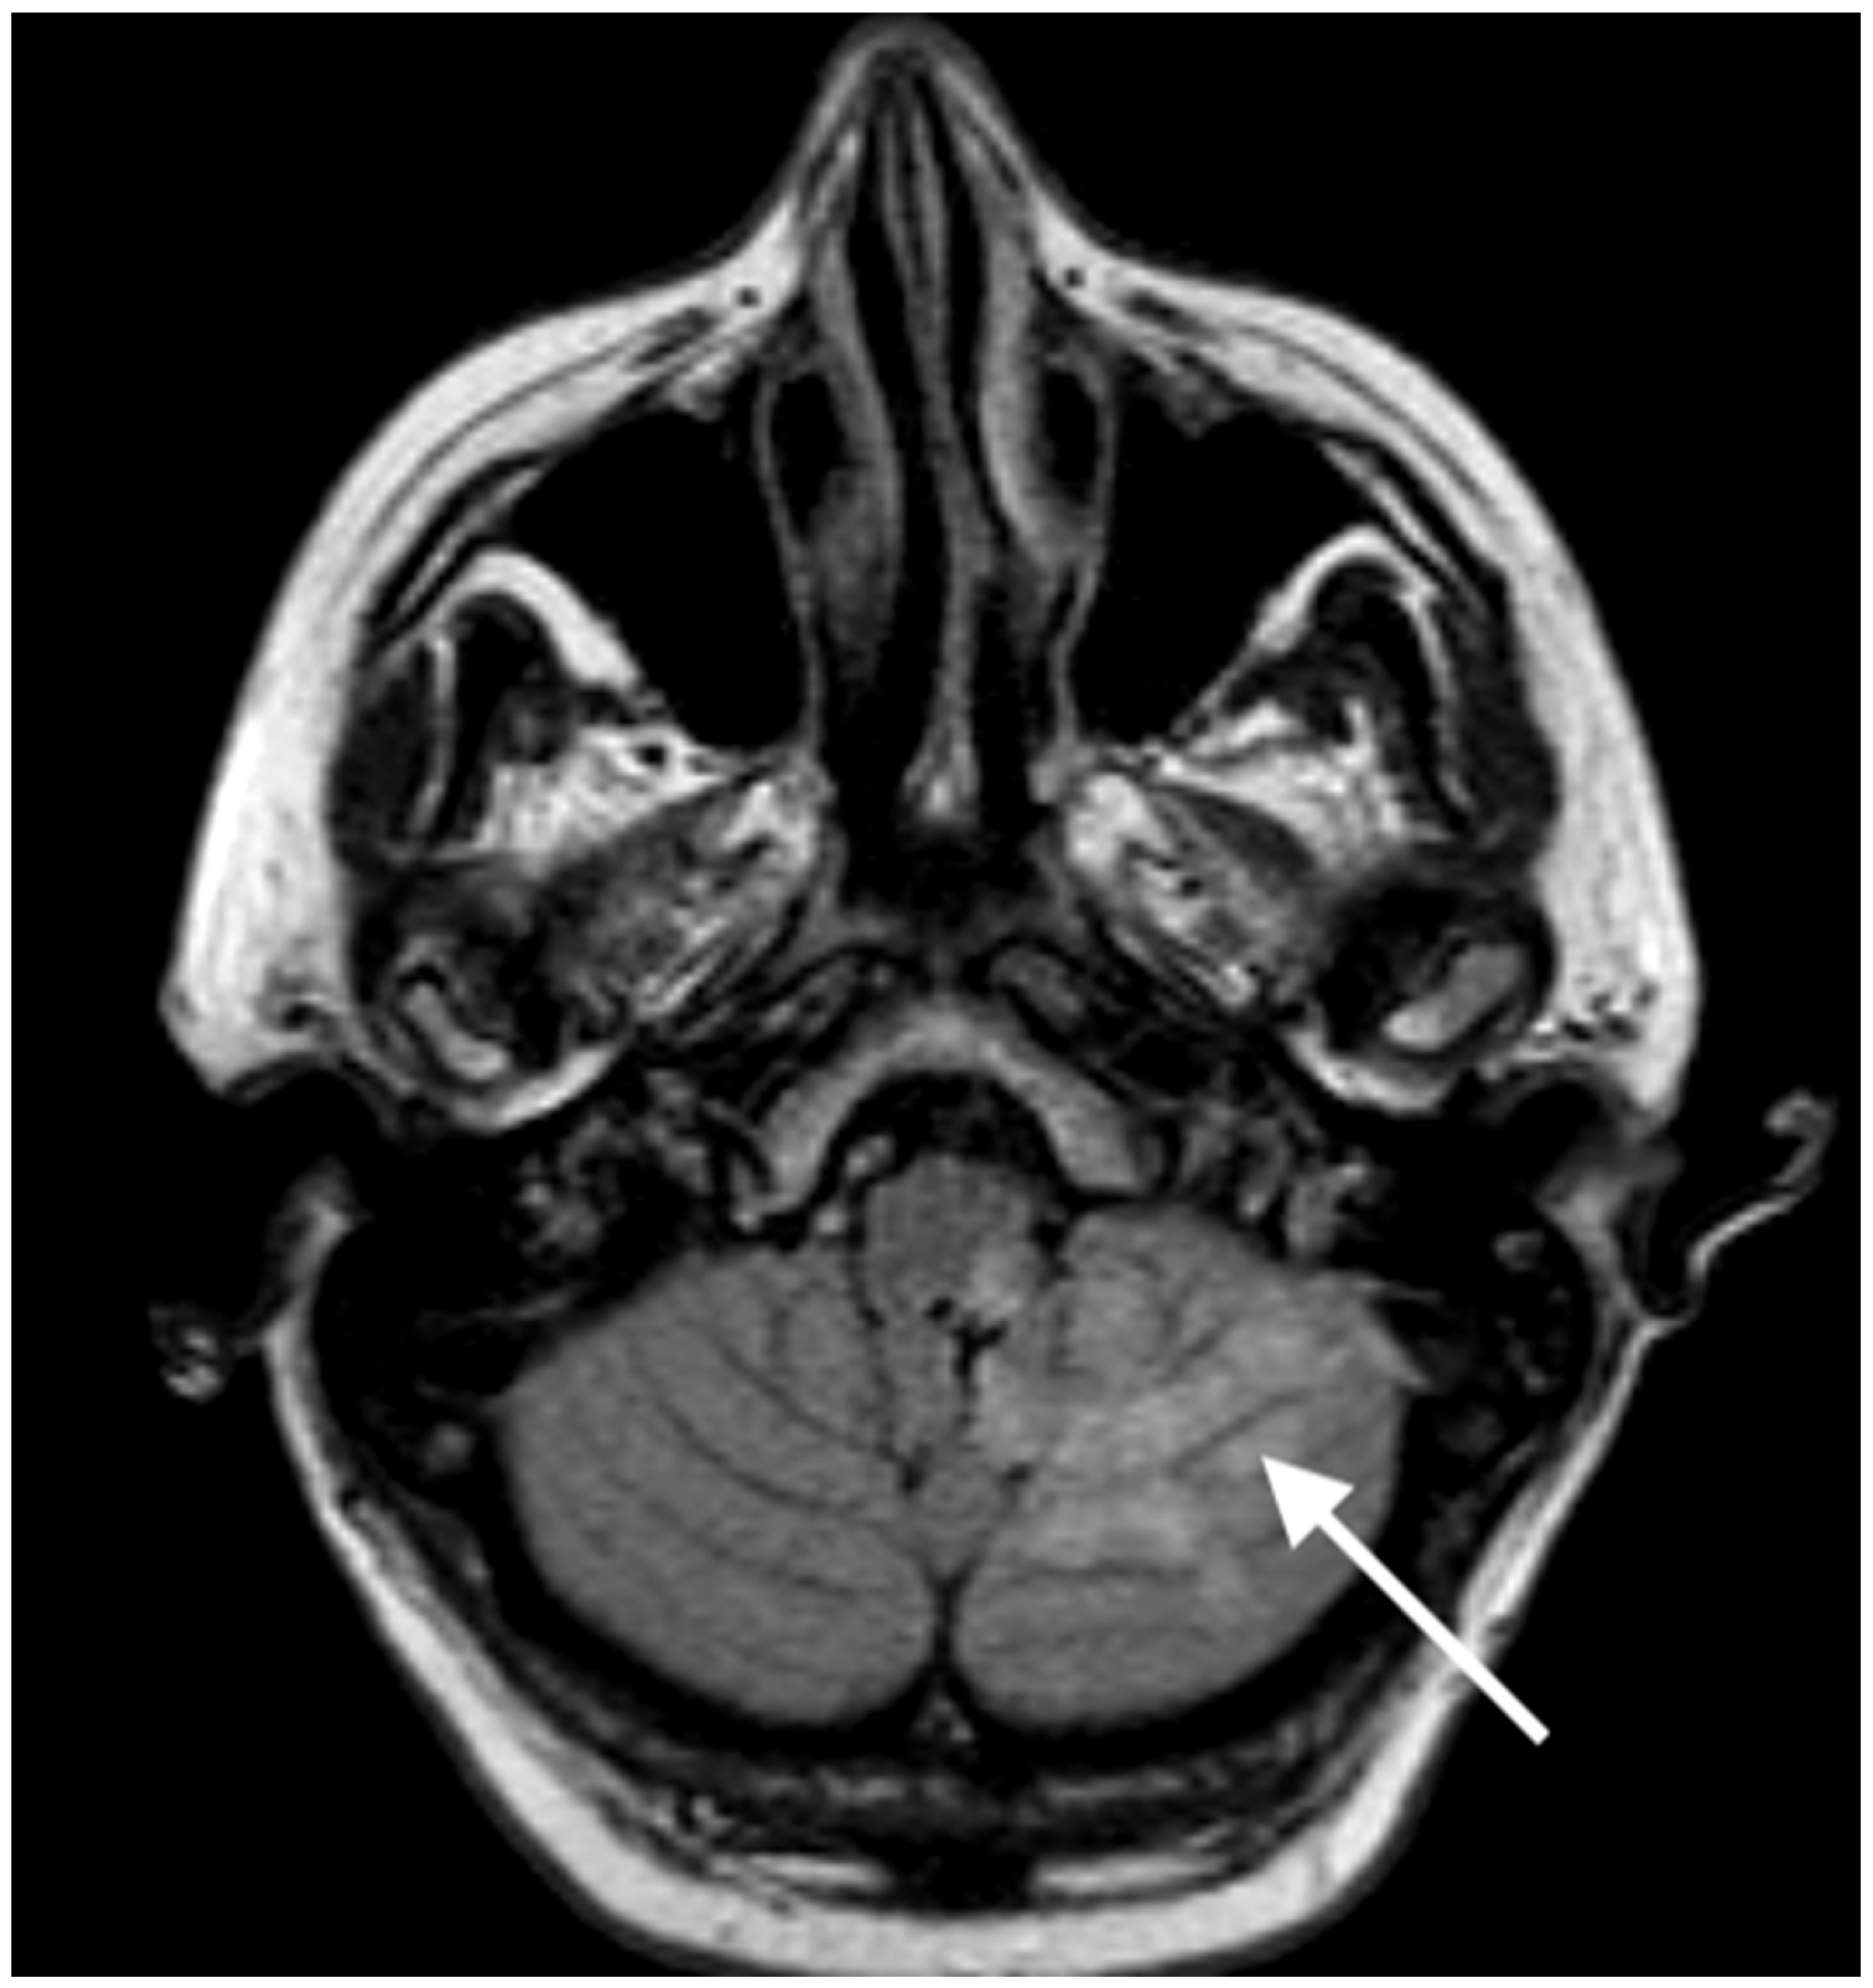

2. Case Report